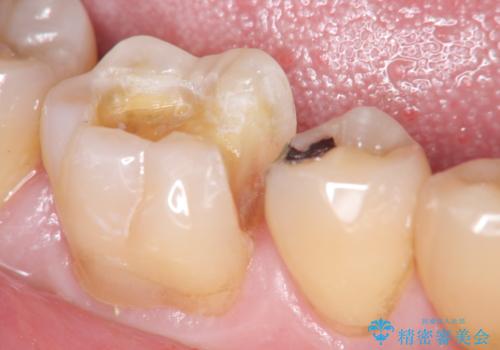

歯の神経を残す、丁寧な虫歯の除去

- 銀歯の劣化、歯のしみる症状の改善を求めて来院されました。

マイクロスコープ、拡大鏡を用いて治療を行うことで虫歯を取り切ることと必要以上に歯を削らず真剣を温存することのできる確率が高まります。

虫歯治療後の予後をより良くするために、虫歯を取り切ること精密な修復物の装着が必須となります。